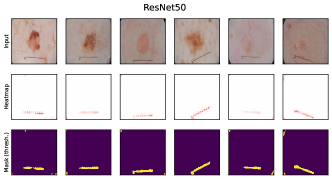

where denotes element-wise multiplication. This yields a heatmap that can be used as a soft mask or converted to a binary segmentation mask, for instance using thresholding techniques like Otsu’s method [57]. An example is shown in Fig. 2 (right), showing soft masks as heatmaps from concept-conditioned local attribution scores, along with binary masks for three known data artifacts: rulers and band-aids for skin cancer detection, and pacemakers in chest radiographs.

6.4 Spatial Bias Localization

To spatially localize biases in input space with CAVs, we compute local explanations for the element-wise product of latent activations and concept direction (see Eq. 2). We use the controlled artifacts, specifically timestamp (HyperKvasir) and micropscope (ISIC2019) with ground truth concept localization masks for evaluation. We compute (1) the percentage of relevance within the ground truth mask and (2) the Jaccard index, or Intersection over Union (IoU), of the binarized localization mask with the ground truth. In Fig. 9, we report both metrics using CAVs computed on different layers of VGG16 and ResNet50. The layer choice for concept representations is key, as for example middle layers perform better to localize timestamps and earlier layers are more effective to localize the microscope. In comparison with Fig.7, we find that the optimal layer for bias localization may differ from the one for sample retrieval. Interestingly, the IoU for the microscope artifact is consistently low, as models primarily focus on the border of the circle instead of the entire area, as indicated by qualitative results in Appendix A.6.3. Unlike artifact relevance, the IoU metric also measures how much of the expected areas the computed mask does not cover.